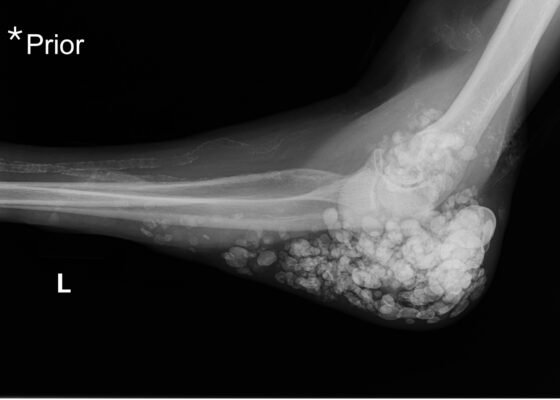

Metastatic Calcinosis Cutis in the Emergency Department: A Case Report

DOI: https://doi.org/10.21980/J87Q00X-ray imaging was obtained of the left elbow and showed soft tissue calcium deposits. Radiology stated, “massive periarticular calcinosis of renal failure obscures fine osseous detail. Several of the largest calcifications have decompressed since the prior exam and may contribute to the drainage observed clinically. Superimposed infection is not excluded.” X-rays with an asterisk are the comparison images from two months previous to the visit. Areas of decompression are highlighted in blue demonstrating that some of the larger calcified nodules are no longer present.